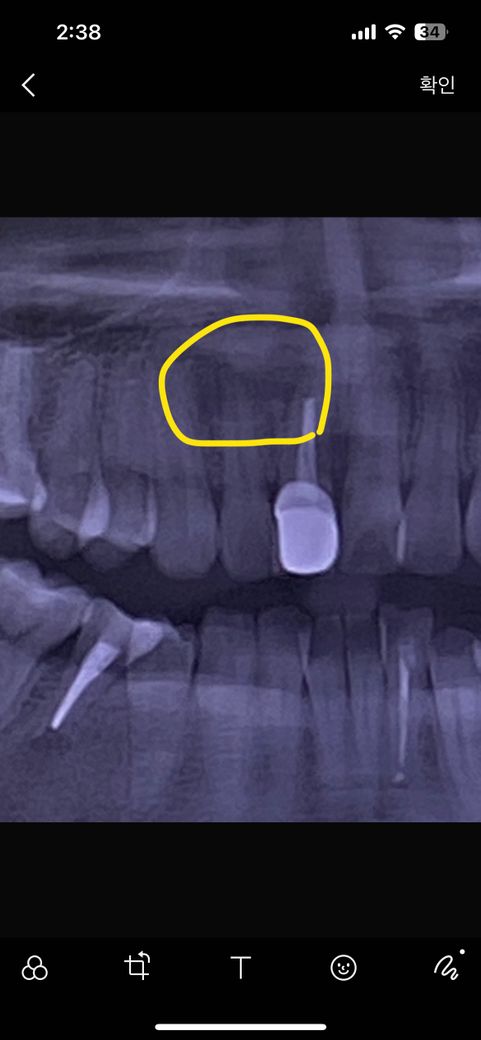

제가 앞니 치근단 병소 때문에 대학병원 수술 예정입니다. 올해초에 찍은 사진이라 지금은 부위가 조금 더 커졌어요. 수술 날짜를 기다리고 있는데 수술하기로 한 옆에 앞니의 잇몸이 좀 드러난것 같아서요.

표시해 놓은 쪽이 수술예정이에요.

염증이 깊어보입니다.

-치아 뿌리끝 염증이 활성화 되면 다른치아에 까지 영향을 줄수 있습니다.

-치과마다 다르겟지만 전신마취 까지 할정도로 심해보이진 않습니다. 다른 치과도 한번 상담을 해보세요.

-염증을 긁어 내고도 염증이 사라지지 않는다면 치근단 절제수를 하셔야될수도 있습니다.

사진으로 봤을 경우 치근단 부위의 병소가 커 보입니다.

치근단 병소의 원인을 확인하고 치료를 하는것이 좋으며 치근단 병소가 없어지지 않는다면 치근단 수술을 해야 할수 있습니다.